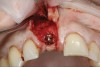

(17.) Implant placed 1-mm distal to the midline of the edentulous space, corresponding with the planned location of the gingival zenith. Note the lack of sufficient bone buccal to the implant that necessitated further grafting.

Figure 17

Prior to the initiation of the surgery, the surgical guide was tried in to confirm proper seating and stability (Figure 15). A flapless approach was not considered because the need for further bone grafting at the time of implant placement had been anticipated through the digital planning. A slightly palatal crestal incision was made, followed by two vertical incisions on the mesial and distal aspects of the edentulous site in order to preserve the papilla and avoid additional esthetic compromise to the anterior sextant. Next, a full-thickness flap was elevated to facilitate removal of the tenting screw and permit visualization of the buccal plate (Figure 16). A standard guided protocol was followed to place the implant, and its final position mirrored that of the digital plan. As predicted, the prosthetically driven implant position resulted in an insufficient buccal plate (Figure 17); therefore, additional guided bone regeneration was performed to reinforce the area and prevent future breakdown (Figure 18 and Figure 19). Making periosteal incisions could have compromised the blood supply to the flap, so instead, it was stretched in order to achieve tension free coronal advancement.31The flap was secured utilizing horizontal mattress sutures with additional supportive interrupted sutures to ensure primary closure (Figure 20). An immediate postoperative periapical radiograph (Figure 21) and CBCT scan (Figure 22) were taken, demonstrating a final implant position centered with the planned location of the gingival zenith.